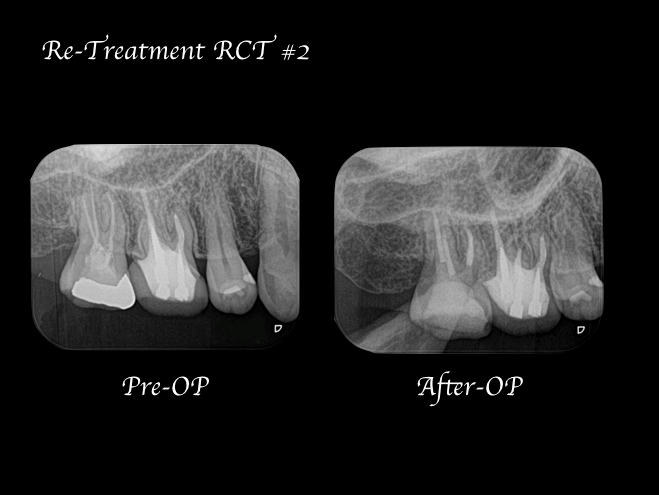

右上7番には臨床症状(叩くことでの痛み)が確認できるものの、レントゲン上には根尖性歯周炎と判断できる透過像(病変の影)は確認できませんでした。歯科用CTを撮影してみると、近心根と遠心根に明らかな病変を認めました(歯科用CT画像1赤丸)。他の臨床症状と歯科用CT画像から右上7番の根尖性歯周炎と診断しました。

治療中に歯科用顕微鏡(マイクロスコープ)下にてCT画像で確認した部位には手つかずの根管を確認し、処置を行った。

治療回数は2回で終了しています。2回目の治療終了時には初診時で患者様が訴えていた違和感は改善され、次週、問題なければ仮歯の製作に移行する予定。